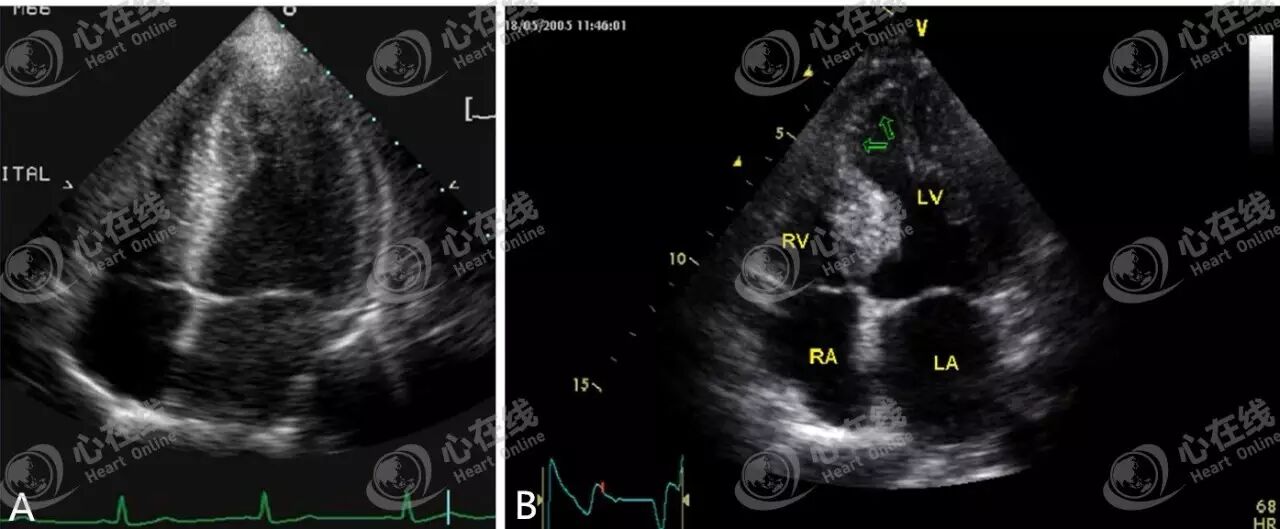

图A显示房间隔缺损,可见房间隔连续中断,血液由左房、途经缺损部位到达右房,后进入右室。图B显示肥厚型心肌病。图C显示室间隔近心尖部有一个连续中断。观察图D可见血流信号从左室经过缺损部位进入到右室。

不同的心尖切面对应不同节段(图A)。四心腔切面显示后间隔和左室侧壁,后间隔的基底段和中间段由右冠状动脉供应,左室侧壁的基底段和中间段由冠状动脉回旋支供应,心尖部由左冠状动脉前降支供应。两心腔切面显示左室前壁和下壁,左室前壁和心尖部由左冠状动脉前降支供应,左室下壁的基底段和中间段由右冠状动脉的后降支供应。三心腔切面显示前间隔和左室后壁,前间隔和心尖部由冠状动脉前降支供应,左室后壁由冠状动脉回旋支供应。

上节课讲到,16节段分法即基底段和肌水平的左室各划分为6个节段,心尖部简化为4个节段(图B)。17节段分法是在16节段基础上多出一节心尖划分,而18节段分法是在16节段基础上不简化心尖部,仍然延续基底段和中间段的6个节段分法。